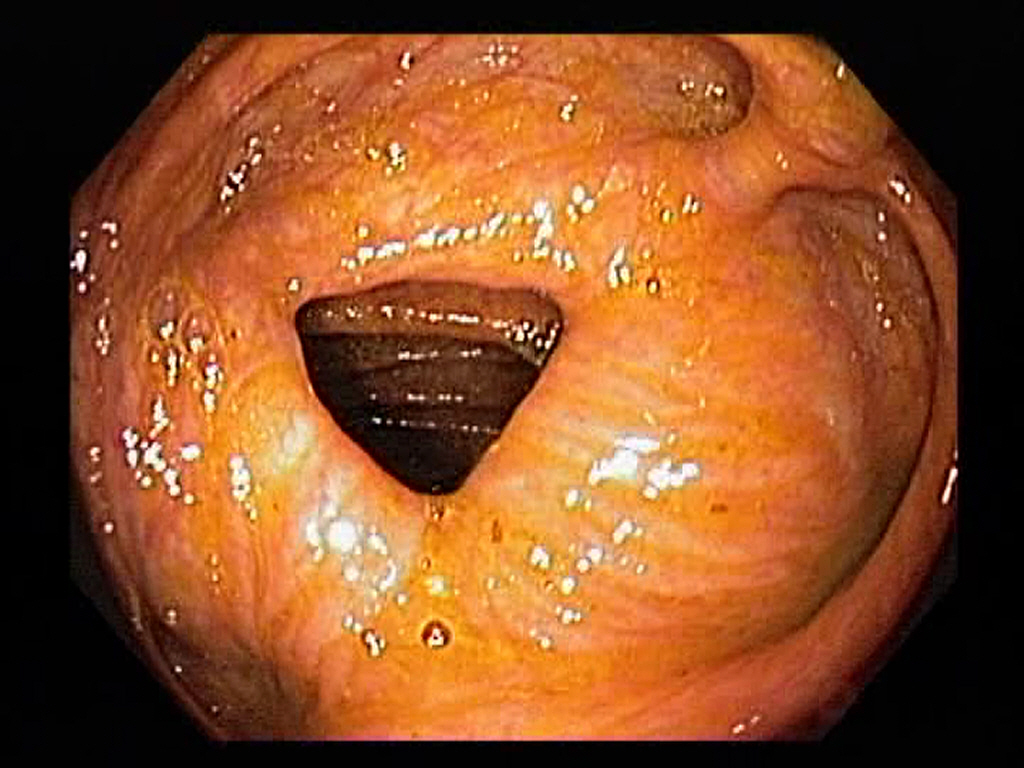

Normal Ascending Colon